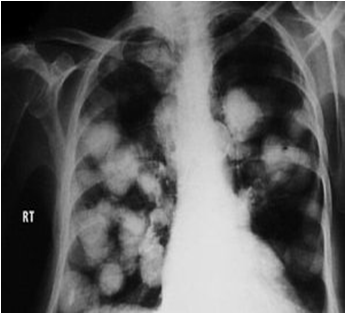

Response rate in small cell lung cancer (SCLC) and a 25% response rate in non-small cell lung cancer (NSCLC). With mesna uroprotection, the primary dose-limiting toxicity is cyclophosphamide/doxorubicin/vincristine) (Figure 1). Among ... Doc Retrieval